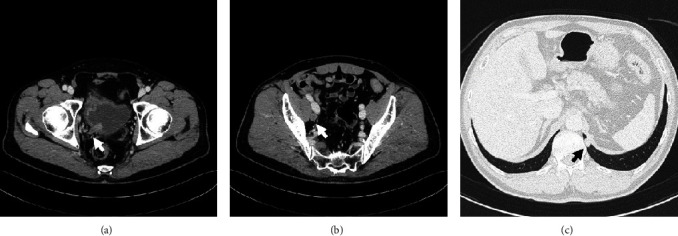

A 64-year-old man was diagnosed with invasive bladder and right lower ureteral urothelial cancer with right pelvic lymph node and lung metastases. He received four courses of gemcitabine and cisplatin therapy. He underwent lung metastasectomy and radical cystoprostatectomy, with not only primary lesions but also metastatic lesions showing a complete response. New multiple lung metastases were revealed five months after adjuvant chemotherapy. On starting pembrolizumab therapy, the metastatic lesions are notably reduced in size. He is currently receiving pembrolizumab therapy, and no recurrence has been observed for over one year.

Abstract Image